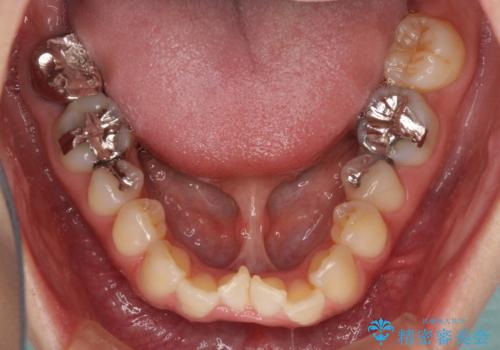

インプラント部は治癒待ちの期間が長くなるため、その期間を利用して下顎の叢生を解消し、より理想的な咬み合わせで補綴治療を行うこととしました。